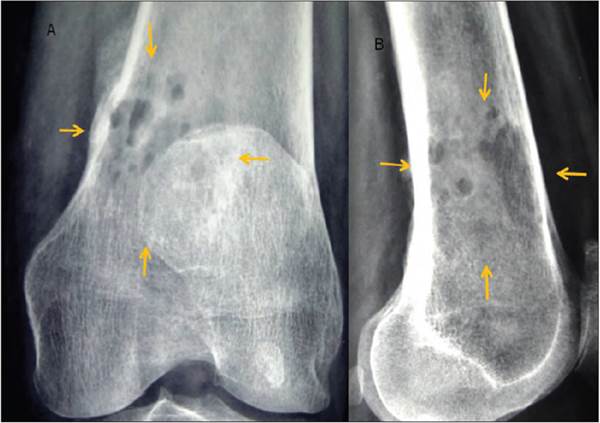

Mujer de 61 años de edad. Inició su padecimiento el 12 de septiembre del presente año con dolor en rodilla izquierda e imposibilidad para deambular. Acude con su médico, quien solicitó radiografías (Figura 6) en las que se observaron imágenes centrales líticas que afectan el tercio distal del fémur izquierdo con edema de partes blandas. Tomografía y gammagrama (Figura 7) que muestra en la fase de equilibrio una zona de hipercaptación con componente mixto de predominio lítico y que involucra la cortical. Se obtiene biopsia y se sospecha diagnóstico de plasmocitoma, motivo por el cual acude a consulta de hematología.

Figura 6 a y b) AP de rodilla y lateral de rodilla que muestra lesiones osteolíticas en tercio inferior (flechas).

En septiembre se obtuvieron nuevas placas de rodilla, ahora con mínimas lesiones, y se decidió tomar nueva RM (Figura 8) que mostró tumor del espacio que afecta la porción central de la médula ósea, del tercio distal de contornos irregulares, espiculados con intensidad de señal heterogénea en todas las secuencias y mostró realce periférico con la aplicación de gadolinio, hipointenso en T1 e hiperintensa en T2, con afectación de la cortical por la toma de la biopsia. En octubre se ajustó el tratamiento con talidomida durante 7 días 2 veces al mes y continúa igual con dexametasona; Se indicó radioterapia a rodilla izquierda para tratar enfermedad residual.